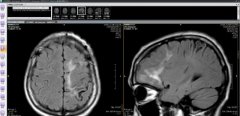

脑软化灶实为虫体在颅内的爬行轨迹;(左)从下往上移动,(右)从后往前移动